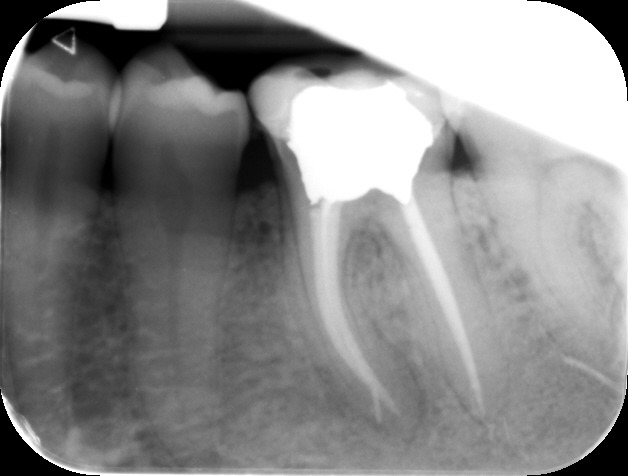

Files of different sizes are used to eliminate bacteria and infection and to shape the canals. The canals are disinfected thoroughly with irrigants and later the canals will be sealed in 3 dimensions with a special medicament called gutta-percha to prevent reinfection of the tooth and the access cavity will be sealed with a temporary filling.

After a few weeks, the tooth will be checked and when all the infection has cleared, a crown will be usually required to protect the restore the tooth to function.